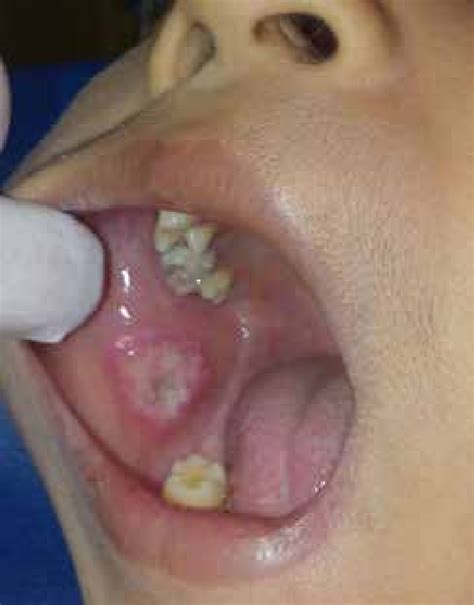

Una erupción vesicular en la parte posterior de la cavidad oral puede sugerir un cuadro de herpangina, mientras que una erupción vesicular en regiones anteriores de la cavidad oral plantea un diagnóstico de sospecha de una (gingivo)estomatitis herpética. Las erosiones en la mucosa queratinizada suelen ser de origen herpético, mientras que las que se producen en la mucosa de revestimiento son más propias de las aftas.

Las erosiones redondeadas suelen tener una etiología endógena (como las aftas) (fig. 12), las lesiones dentelladas son frecuentemente de origen exógeno (como traumatismos), mientras que las formas policíclicas apuntan más bien a una etiología vírica. En general, los tumores pediculados son benignos, mientras que un tumor sésil de base amplia suele ser maligno.

Figura 12. Las erosiones con una forma redondeada sugieren una causa endógena como en el caso de esta afta.